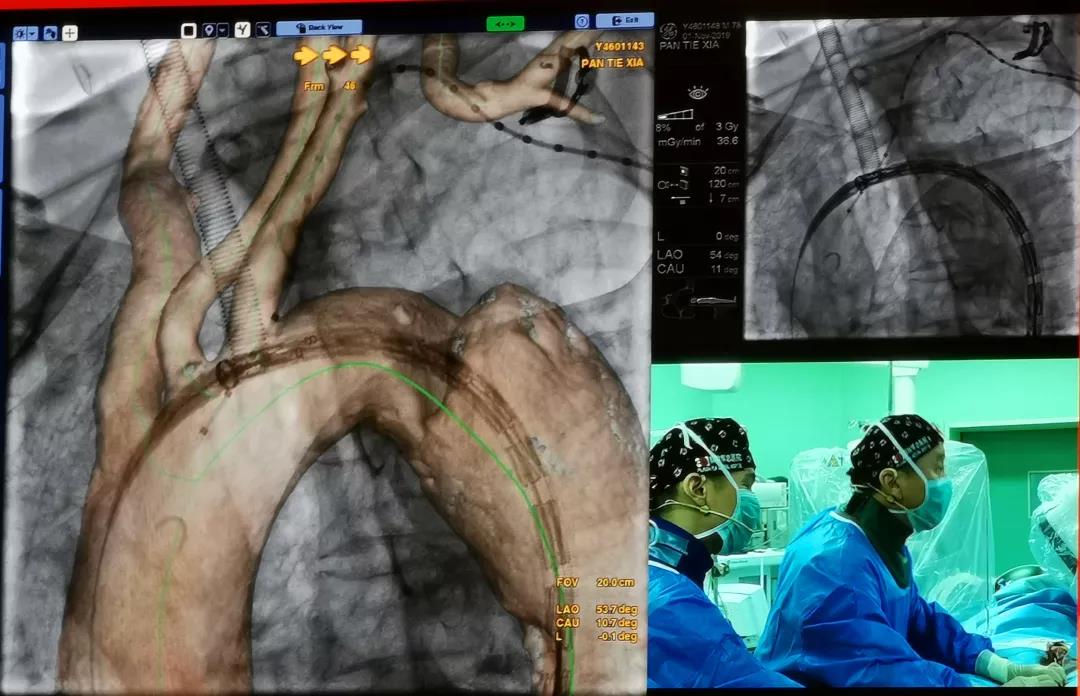

会议期间,首都医科大学附属北京安贞医院、中国人民解放军总医院和复旦大学附属中山医院三家中心,在主会场展示了7台采用彩神在线网信彩票-彩神通免费版下载-彩神8争霸vlll-彩神购彩购彩大厅-彩神软件陆立根免费版-彩神ll争霸3-彩神ll彩神8-彩神ll争霸彩票-拼搏在线彩神网网页版外周产品治疗疑难主动脉病变的实战演示。

中国人民解放军总医院郭伟教授共演示了3台手术,分别是采用Ankura™支架治疗Stanford B型慢性胸主动脉夹层,采用Lifeflow™IBD髂动脉分叉支架系统和Fustar™可调弯鞘在治疗腹主动脉瘤时重建右侧髂内动脉的病例。另外,郭伟教授还演示了一台使用Ankura™支架和新型G-Branch™胸腹主动脉覆膜支架系统重建内脏动脉全腔内修复胸腹主动脉瘤的病例。郭教授从患者病变情况和治疗难点、手术方案、G-Branch™支架产品设计特点及术中操作要点等方面详细介绍了手术过程。手术取得了极大的成功,术后造影显示,瘤体隔绝,内脏四分支血管血流通畅,且主体支架与分支支架连接处无内漏。与会专家对此精彩的病例表示尤为赞叹,积极与郭伟教授探讨G-Branch™支架的创新之处和未来使用方向。郭教授表示,多分支动脉的腔内重建是胸腹主动脉瘤微创治疗的一个技术高地,也是国际性难题。G-Branch™支架的应用,为胸腹主动脉瘤的患者提供了更为优秀的解决方案,期待未来更多的临床应用和循证医学证据将证实其优越性。

复旦大学附属中山医院符伟国教授分别演示了其采用彩神在线网信彩票-彩神通免费版下载-彩神8争霸vlll-彩神购彩购彩大厅-彩神软件陆立根免费版-彩神ll争霸3-彩神ll彩神8-彩神ll争霸彩票-拼搏在线彩神网网页版Fustar™可调弯鞘结合原位开窗技术治疗B型主动脉夹层的病例和运用Ankura™支架+去分支技术联合腔内修复治疗内脏区胸腹主动脉瘤的病例,两例手术均取得了十分满意的效果。